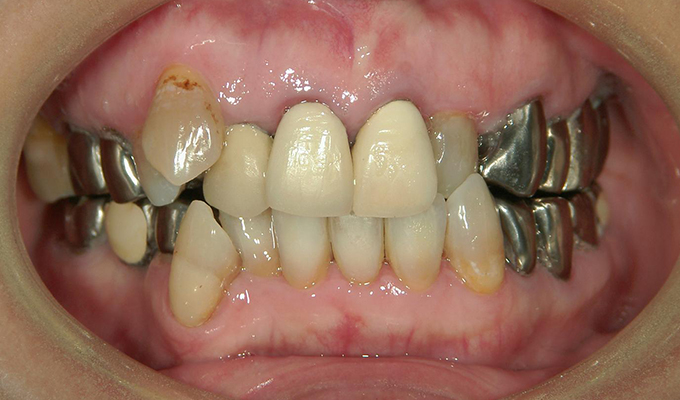

初診時(2010年)

- 5年ほど前に上に総入れ歯を作った。(マグネットタイプ)食事してたら人口歯が取れてしまった。インプラントに興味がある。40代なので入れ歯はやっぱり嫌、とのことでした。

- 上・・・虫歯の根だけの歯が数本残っているためすべて抜歯し仮義歯作成しました。最終的には8本インプラントを埋入し上部構造はメタルボンドです。

下・・・保存できる下の歯はメタルボンドブリッジにし、奥歯のない部分に3本インプラントを埋入しました。治療期間は2年ほどかかりましたがしっかり食事ができるようになったので嬉しいと、満足していただけました。